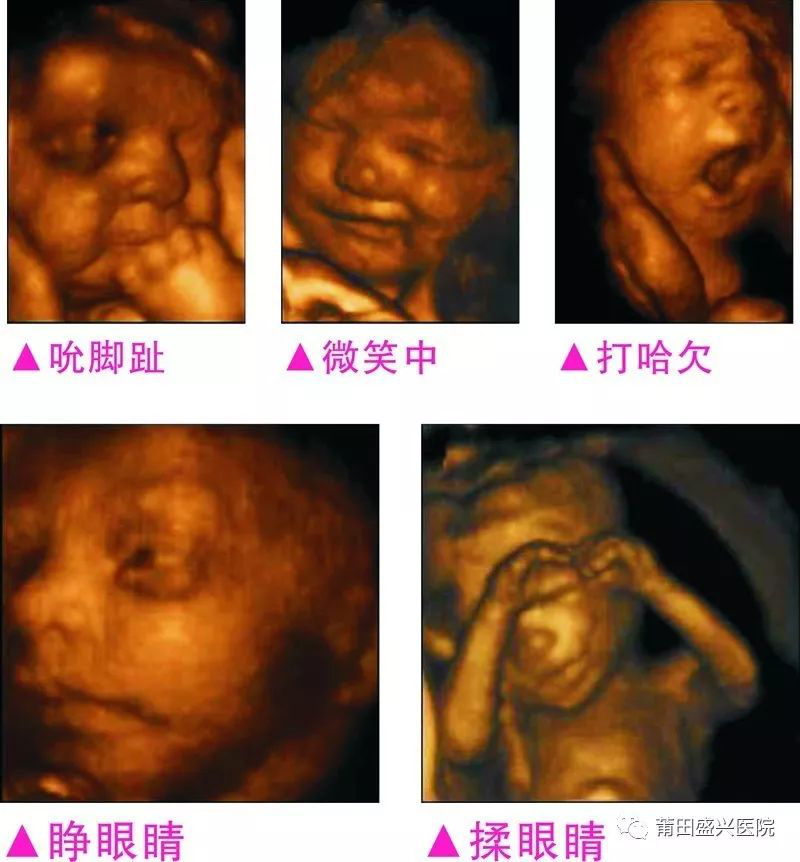

你一定不知道寶寶這么小就有這么多表情

四維容積成像技術(shù),智能光源系統(tǒng)展現(xiàn)梯度亮度,渲染畫面,提高容積成像品質(zhì),高清顯示腹中寶寶的實(shí)時(shí)動(dòng)態(tài)影像,完整記錄寶寶的一舉一動(dòng),讓準(zhǔn)爸媽與寶寶Di一次幸福“見面”,更可刻錄成高清視頻,送給未來寶寶的珍貴禮物。